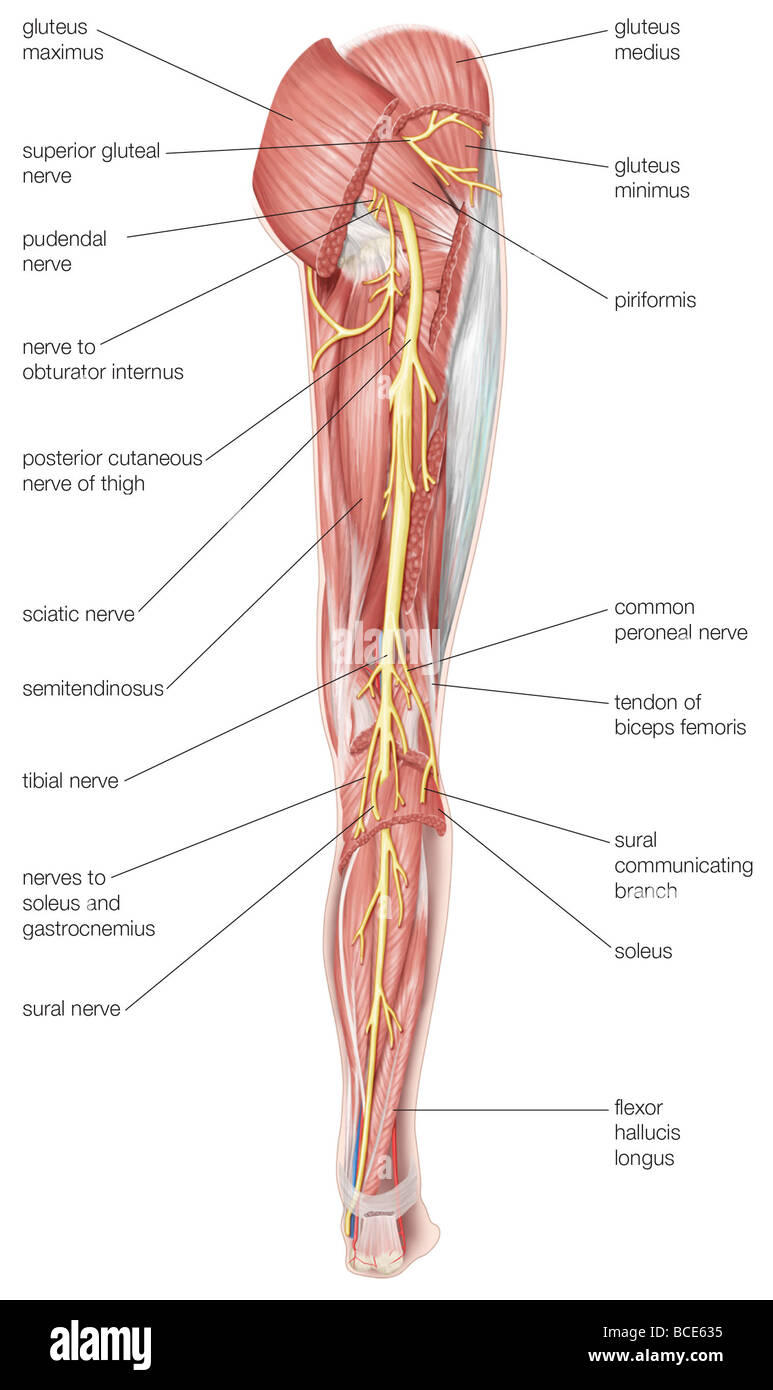

La vue postérieure de la jambe droite, montrant le nerf sciatique et de ses branches. Banque D'Imageshttps://www.alamyimages.fr/image-license-details/?v=1https://www.alamyimages.fr/photo-image-la-vue-posterieure-de-la-jambe-droite-montrant-le-nerf-sciatique-et-de-ses-branches-24898361.html

La vue postérieure de la jambe droite, montrant le nerf sciatique et de ses branches. Banque D'Imageshttps://www.alamyimages.fr/image-license-details/?v=1https://www.alamyimages.fr/photo-image-la-vue-posterieure-de-la-jambe-droite-montrant-le-nerf-sciatique-et-de-ses-branches-24898361.htmlRMBCE635–La vue postérieure de la jambe droite, montrant le nerf sciatique et de ses branches.